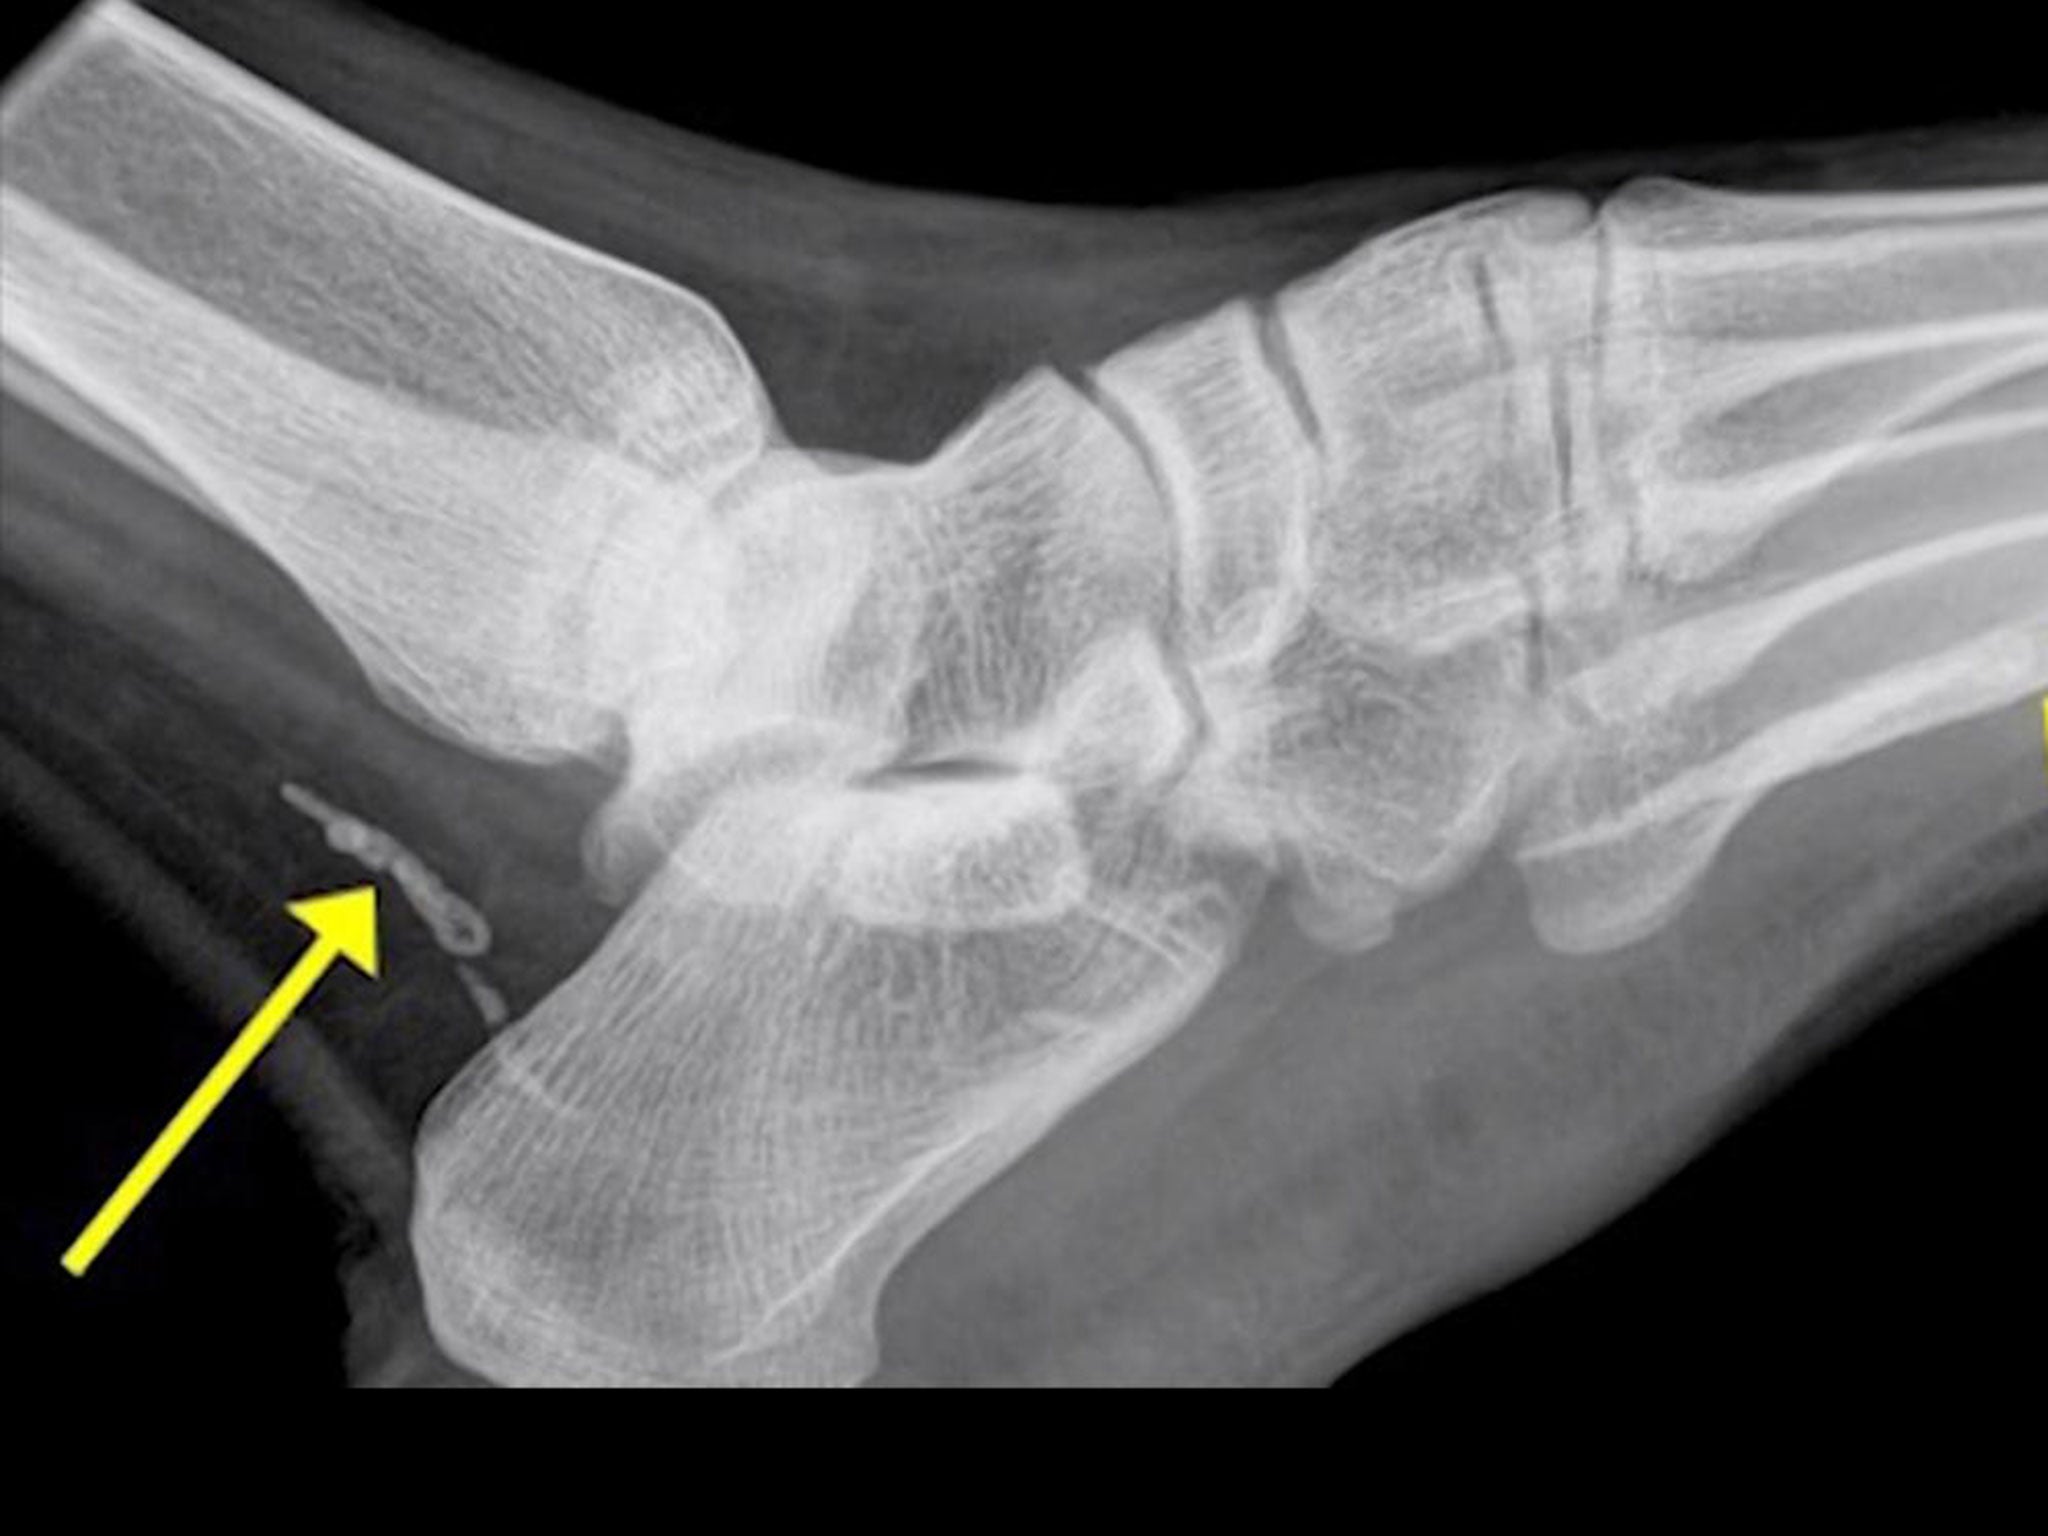

A X-ray on a man complaining of a swollen foot revealed a parasitic worm capable of growing up to a metre long had been living inside him for years.

However, an X-ray found what appeared to be two pieces of "guinea worm" or Dracunculiasis medinensis in his ankle and foot, a parasite still found in Africa. Adult females can grow up to one metre long.

Mr Darby said the parasite discovered in his patient’s ankle was split into two and was only centimetres long because it had most likely died and begun disintegrating.